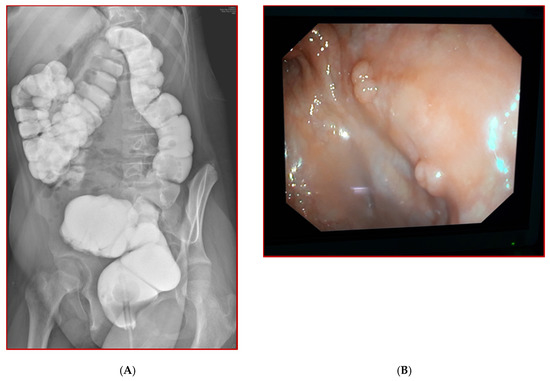

3.1. Case 1

3.2. Case 2